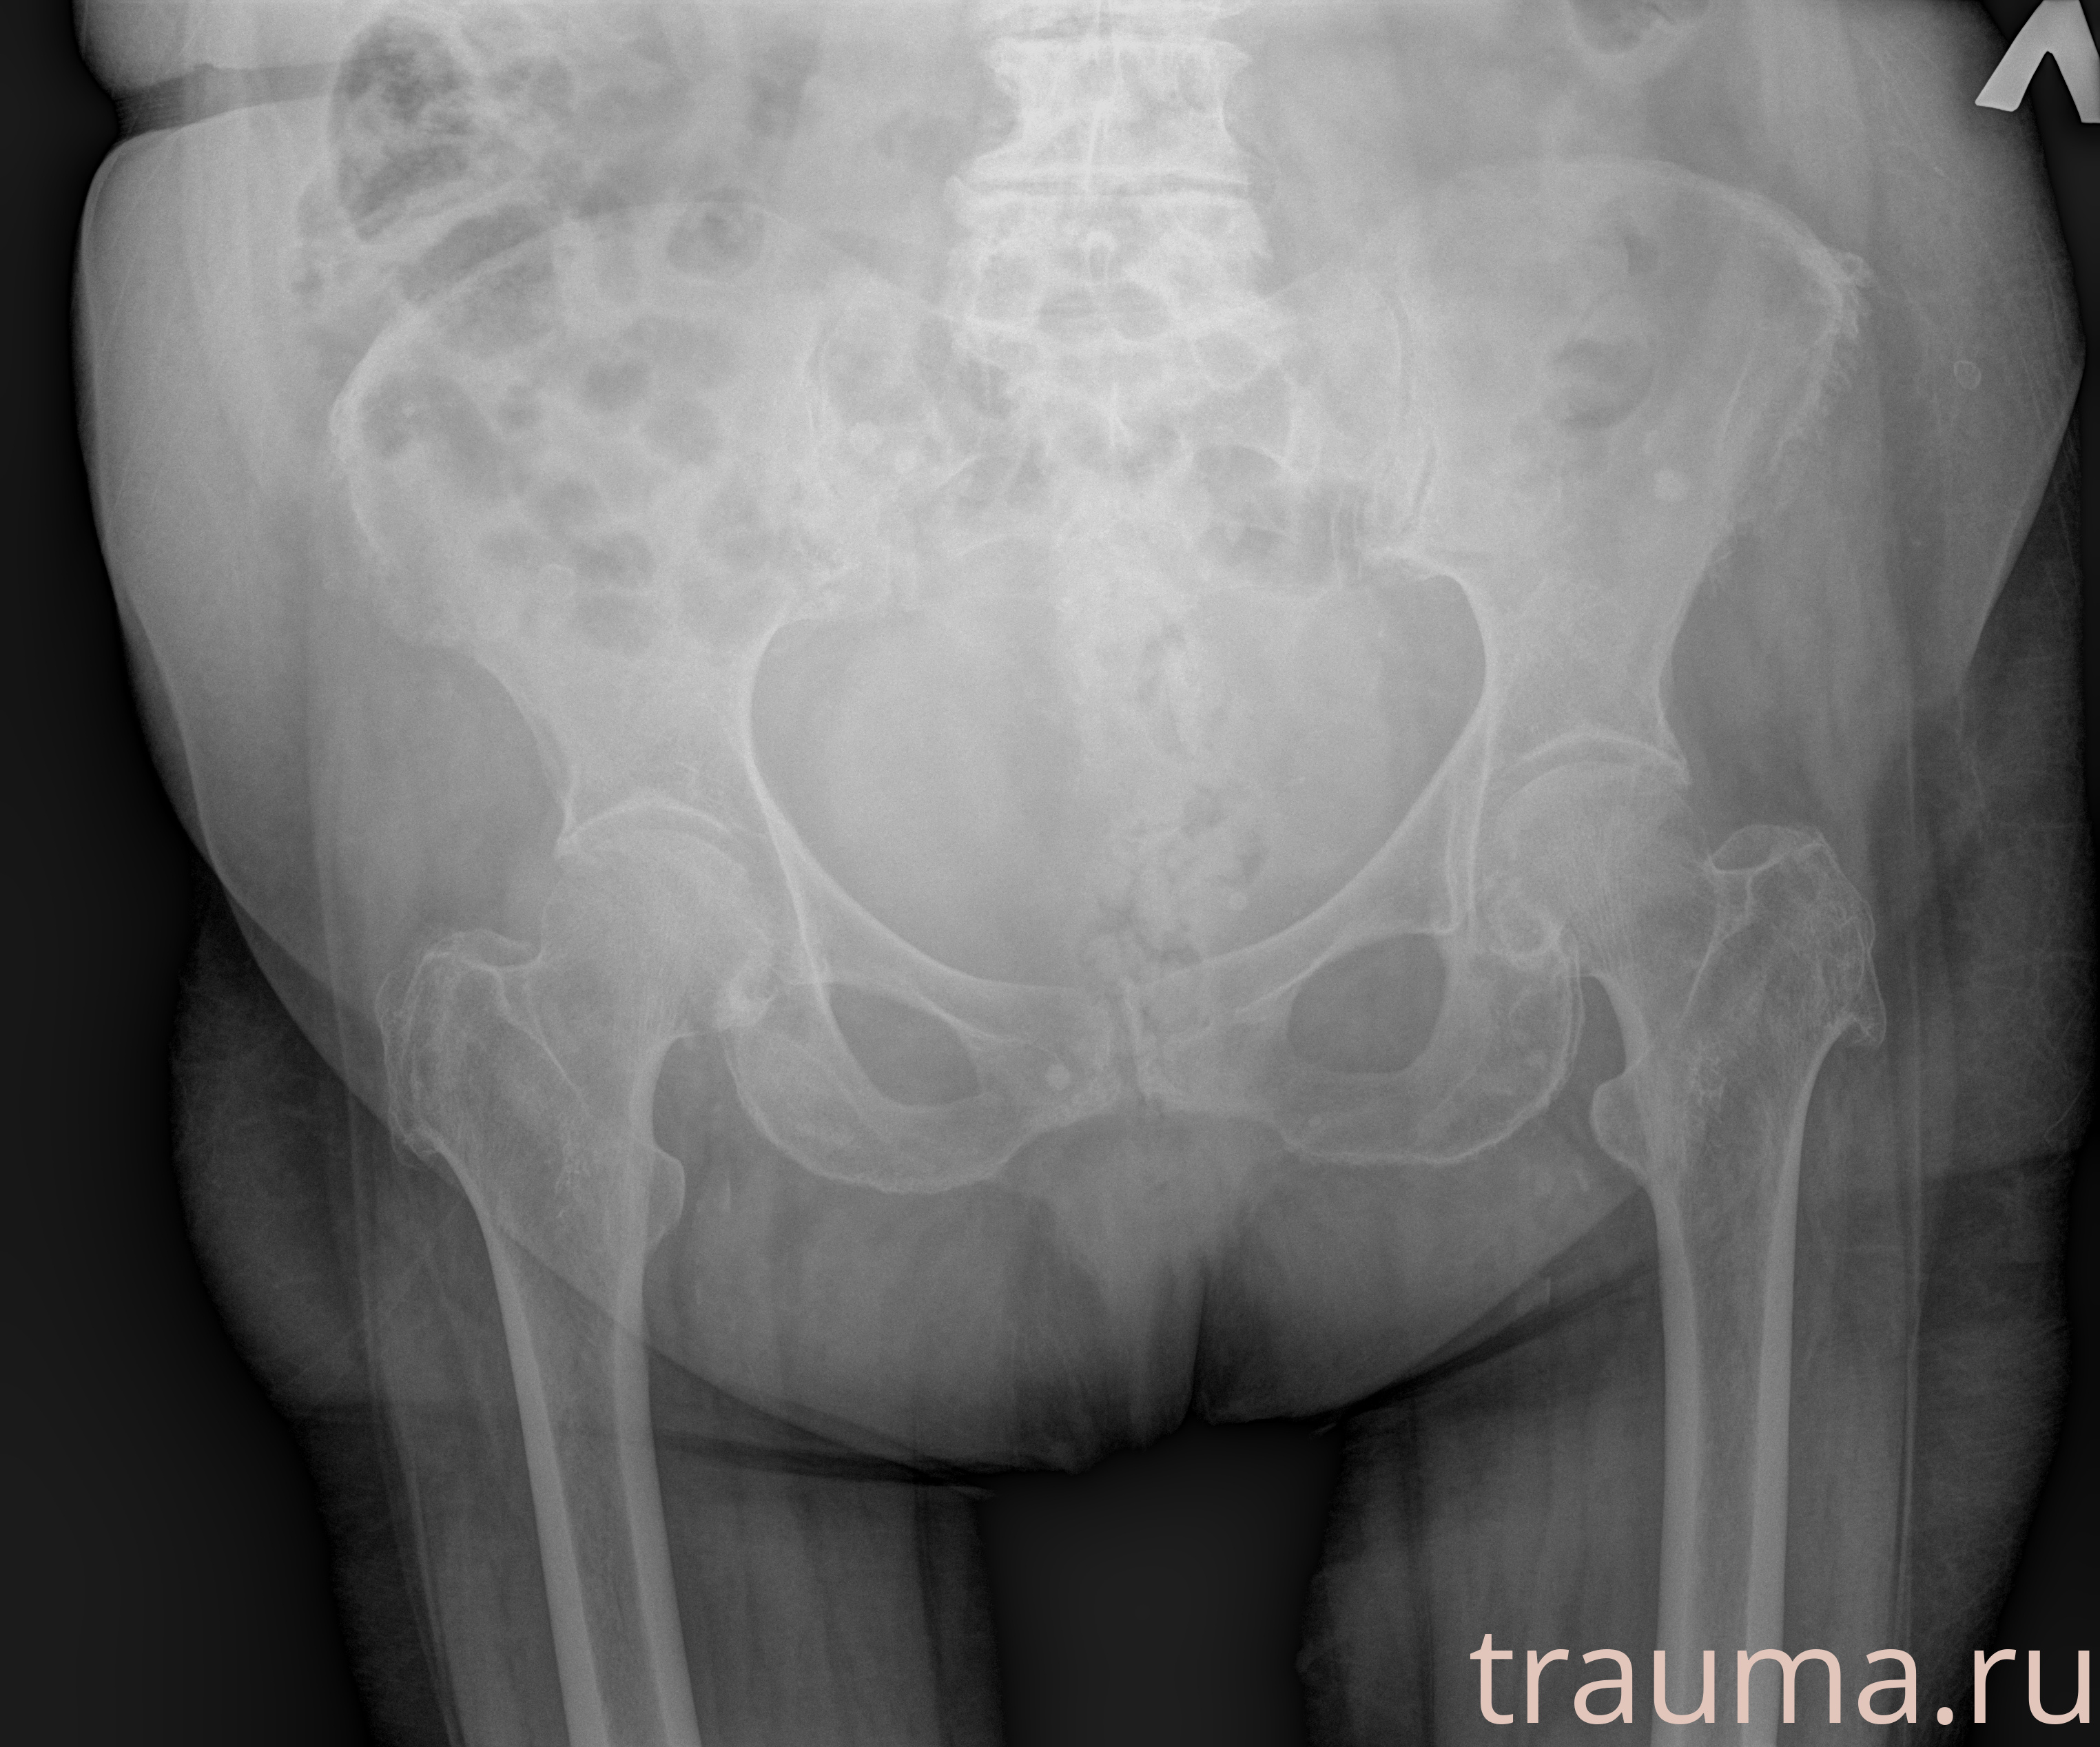

Первая помощь при переломе шейки бедра

Рентген на дому: по вашему адресу приезжает врач-рентгенолог, травматолог-ортопед с мобильным рентгеновским аппаратом, проводит диагностику травмы или заболевания, делает необходимые рентгенограммы, дает рекомендации по дальнейшему лечению. Получить качественные снимки в домашних условиях возможно благодаря уникальной методике, разработанной МосРентген Центром для института  Склифосовского